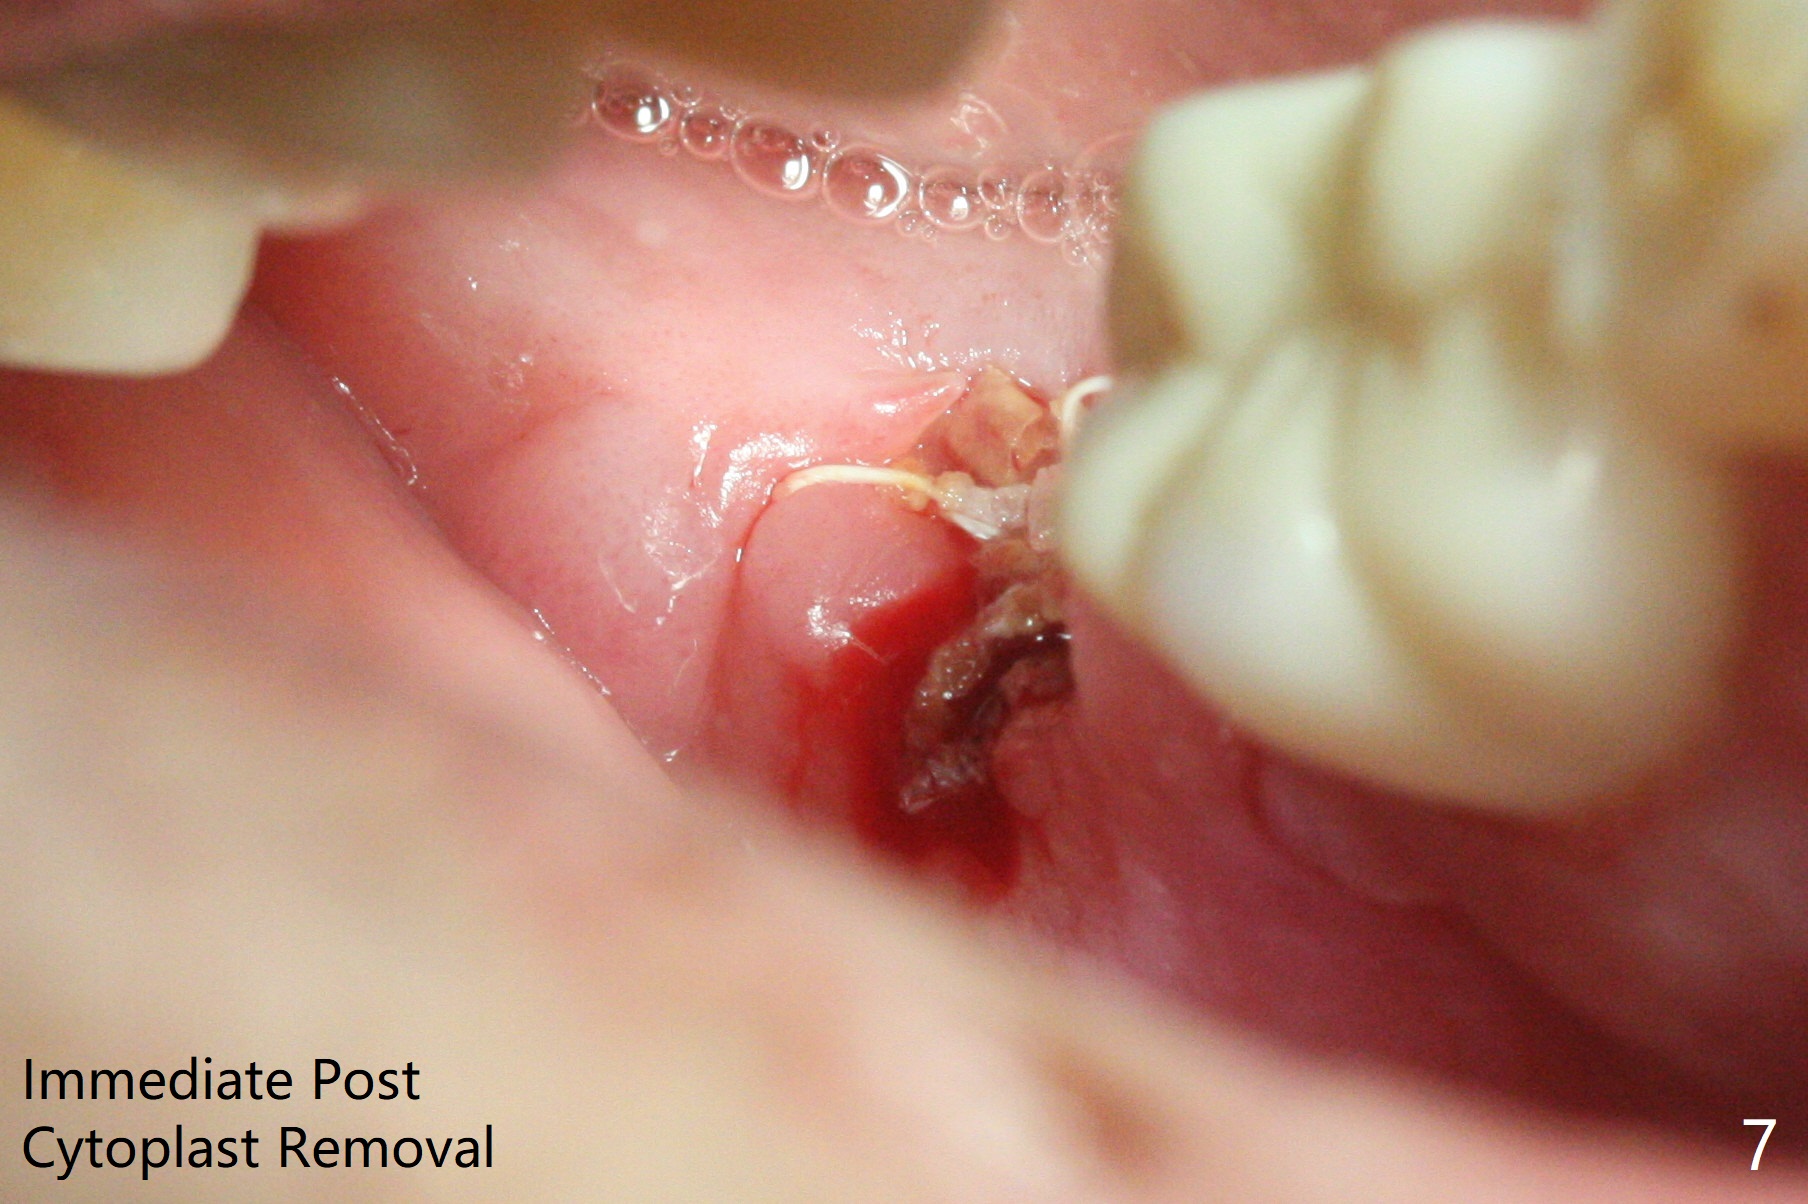

A 67-year-old man returns for periodic exam and #19 impression (Fig.3), which is impossible because there is open bite on the left (Fig.1 *). The latter is related to several periodontal abscesses (supraeruption, Fig.1,2). His chief complaint is mobility of #31 (Fig.3,4). Due to severity of infection, #31 is extracted with bone graft retained by Titanium-Reinforced Membrane (Cytoplast, Fig.5 T). PTFE suture is used. It is easy to tie knots with this non-resorbable (absorbable) suture. The Titanium-Reinforced Membrane exposes 1.5 months postop (Fig.6), which makes its removal easy (Fig.7). In fact the patient is pre-diabetic.